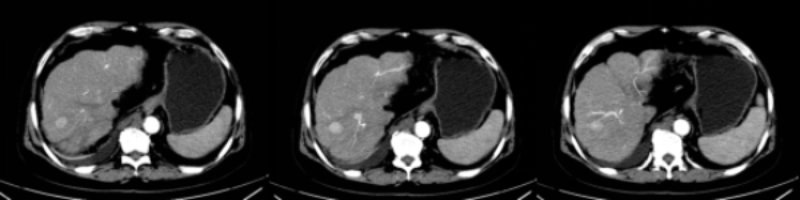

近日,68岁的杨大爷(化名)因“反复腹胀9年,再发1周”来我院就诊。在医生详细询问下,得知杨大爷既往有“乙肝、肝硬化”病史9年,收住感染科,入院后完善腹部增强CT显示:考虑肝S8肝癌;肝硬化、脾大、腹水、门脉高压,侧支循环形成;腹腔多发增大淋巴结;门静脉主干及分支栓子。请肿瘤科会诊,会诊考虑到杨大爷肝肿瘤临近横膈,大小约2.2cm,肝硬化失代偿期,Child-Pugh B级,手术风险大,综合病情,医生建议杨大爷行CT引导下经皮微波消融治疗肝肿瘤,在获得了患者及其家属的同意后,杨大爷转入到肿瘤科进行微波消融术。

经过1个多小时的手术,肿瘤消融完全,周边组织损伤很小,手术过程十分顺利,杨大爷表示没有任何不适,耐受性良好。1个月后返院复诊,CT提示肝肿瘤完全灭活。

术前肝肿瘤情况,邻近横膈

1个月后复查CT提示肝肿瘤完全消融